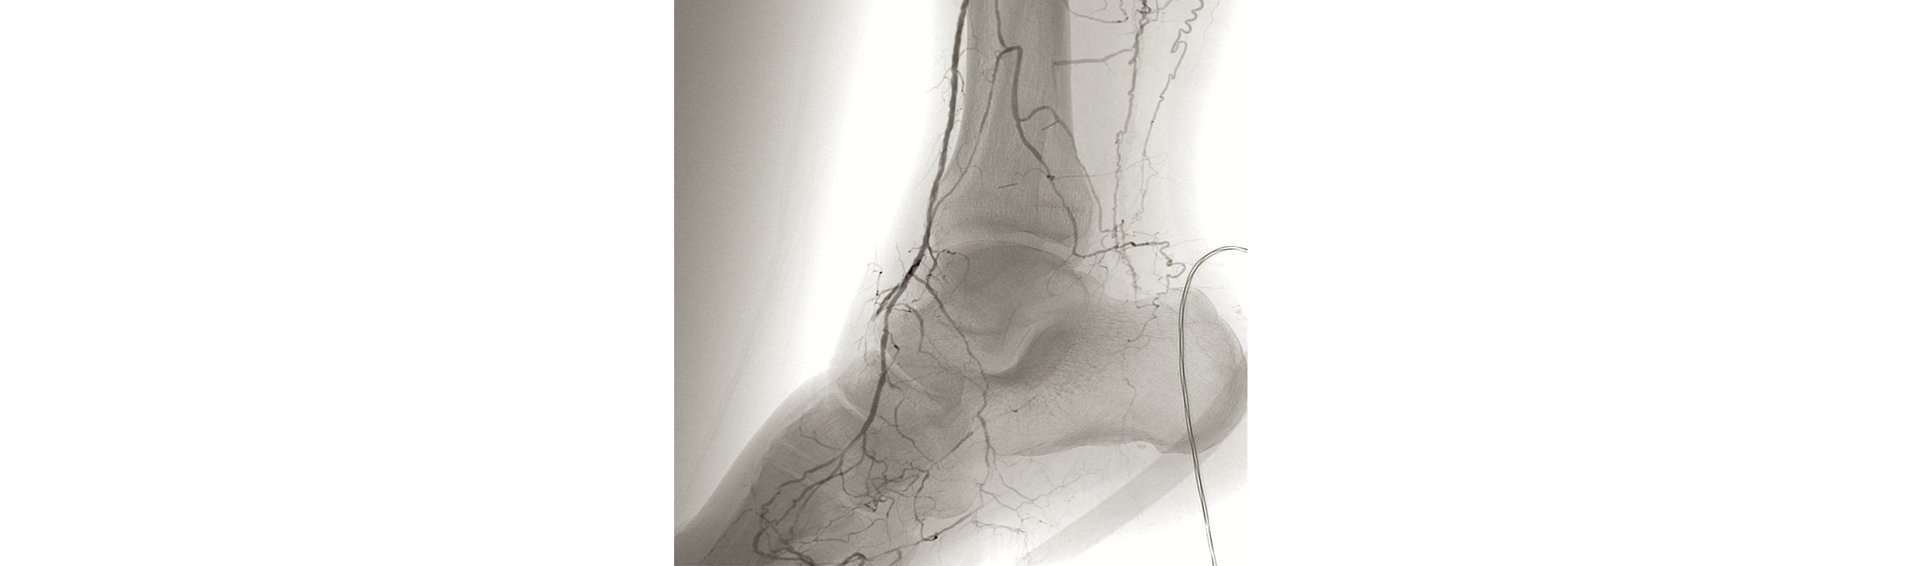

Narrowing of the arteries can usually be treated by balloon dilatation and stent implantation. A balloon dilatation is an operative measure, in which a catheter is introduced into the artery through a hypodermic needle, carrying an inflatable balloon. The balloon can be inflated with high pressure, so to expand a narrowed blood vessel (vasoconstriction). In most cases, a specifically designed wire mesh grid (stent) is inserted to secure the resulting outcome, which is placed keep the vessel open. Longer or larger closures are bridged with a bypass (collateral circuit). The great saphenous vein (a large vein that runs under the skin on the side of the leg) or plastic vascular prostheses can be used as a bypass material. In some cases, the small saphenous vein (which runs under the skin of the lower side of the thigh) is used as bypass material. Although rarely, even veins of the arm (cephalic or basilic vein) can be used. Vasoconstrictions or short narrowings/occlusions in the femoral arteries are treated by endartectomy. The plaque (deposition in the vessel) is peeled or scraped off with a special instrument (spatula) and the vessel incision extended by a patch. Here too, a vein, plastic or bovine pericardium (modified pericardial bovine tissue) can be used for the to be sewn-in patch.